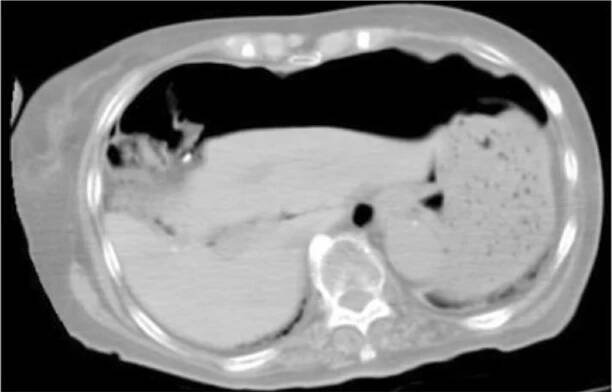

Computed tomography findings show a massive pneumoperitoneum